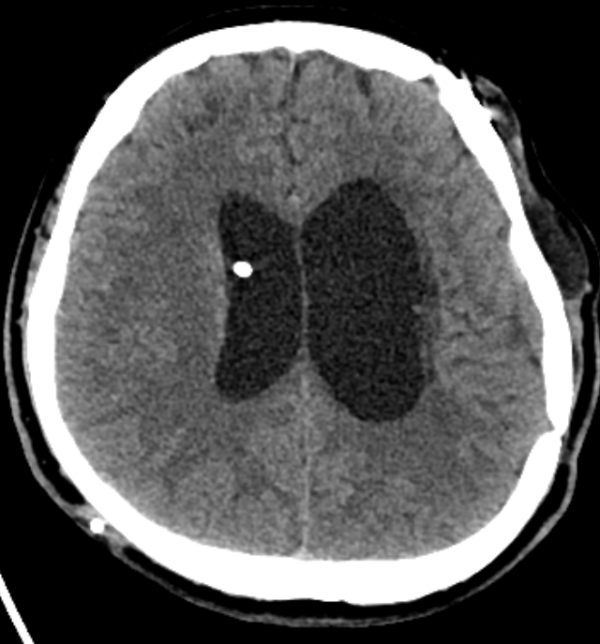

9.MRI에서 나타나는 대표소견 아래와 같이 나타남.

FLAIR : intraventricular debris layering

T1 contrast : ependymal enhancement

DWI : restricted diffusion (pus)

Hydrocephalus

뇌실염 MRI에서 ependymal enhancement + intraventricular debris 가 특징적, EVD 및 Shunt 삽입력이 있으면 뇌실염 가능성이 훨씬 높음.